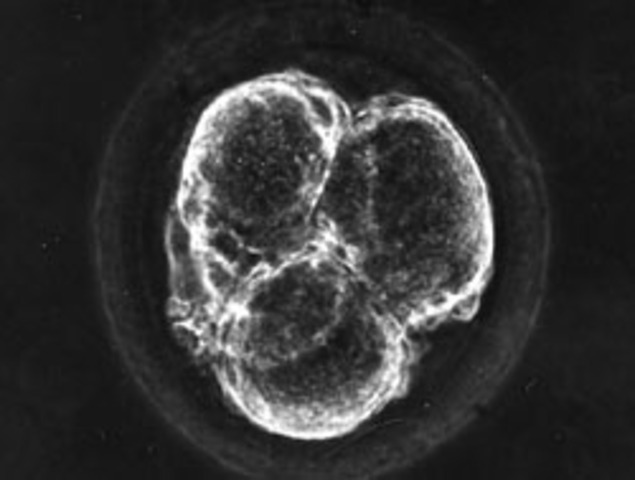

Prenatal Development- Germinal Stage

The germinal stage is the first and shortest stage of the prenatal period. This is when the zygote begins to divide and grow in complexity during the first two weeks following conception. During the germinal stage, the fertilized egg travels toward the uterus, where it becomes implanted in the uterus's wall. Picture- faculty.tcc.fl.edu